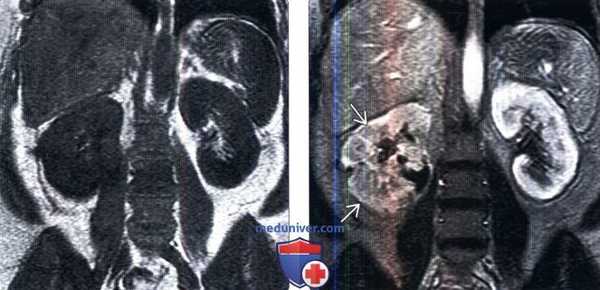

(Слева) МРТ почек, Т1-ВИ, коронарная проекция: аномалии не обнаружены.

(Справа) МРТ, контрастирование Гд, Т1-ВИ, коронарная проекция: у этого пациента выявлено снижение перфузии по всей правой почке из-за тяжелого пиелонефрита.